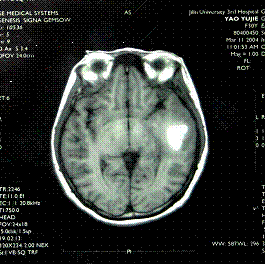

6.腦CT檢查;CT診斷顱內腫瘤主要是根據腫瘤組織的密度改變和腫瘤對腦室系統的壓迫移位來判斷。有些腫瘤顯示密度高,CT圖像清晰;有的腫瘤因有鈣化沉著,對比清楚;有些腫瘤或因瘤組織壞死,或因病灶周圍水腫等變化而顯示為均勻或不均勻之低密度區。顳葉腫瘤多為膠質瘤和腦膜瘤,CT檢查多顯示為高密度區,亦有少數腫瘤有鈣化,囊變、壞死、水腫等顯示其不同的密度變化。側腦室和第三腦室常見受壓、變形、移位等。